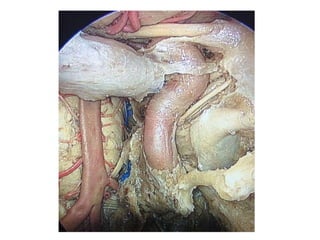

PETROUS APEX CHOLESTEATOMA - Dear surgeons today we did INFRA-COCHLEAR

approach to petrous apex cholesteatoma through BRACKS MANS TRIANGLE

cholesteatoma is completely removed with microscopic approach passing under the

vertical ica It was communicated intradurally Finally cavityis obliterared with fat Here

are some microscopic pics